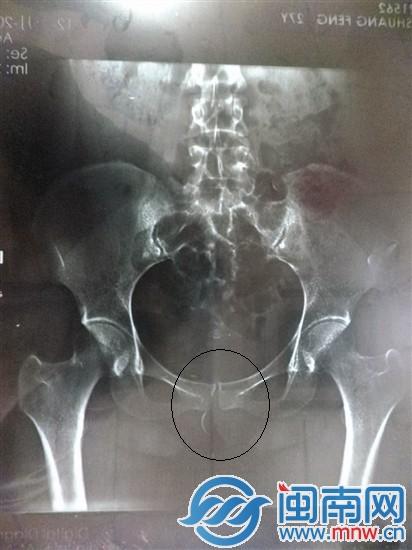

检查后,拍片显示,小傅下体有一根针形异物(画圈处)

随后,夫妻俩又到龙岩市第一医院做透视,检查出,“她体内有弧形的硬物,细细的,3厘米长”。这马上让小宋想起,妻子分娩时,医生做完手术后说过,不见了一枚针的事情。两人又回到龙岩人民医院拍片,才确定小傅的体内确实有一枚弧形针状异物。

对于小宋的怀疑,卢医生称,医院当时所用的缝合针有两个型号,医院也对两个型号的针拍片,并做了影像对比,“经过对比,怀疑小傅体内的针,与医院所使用的针型号是不相符的,从影像看来,小傅体内的针是有孔的,而医院所使用的两种型号的针,都是无孔的。”